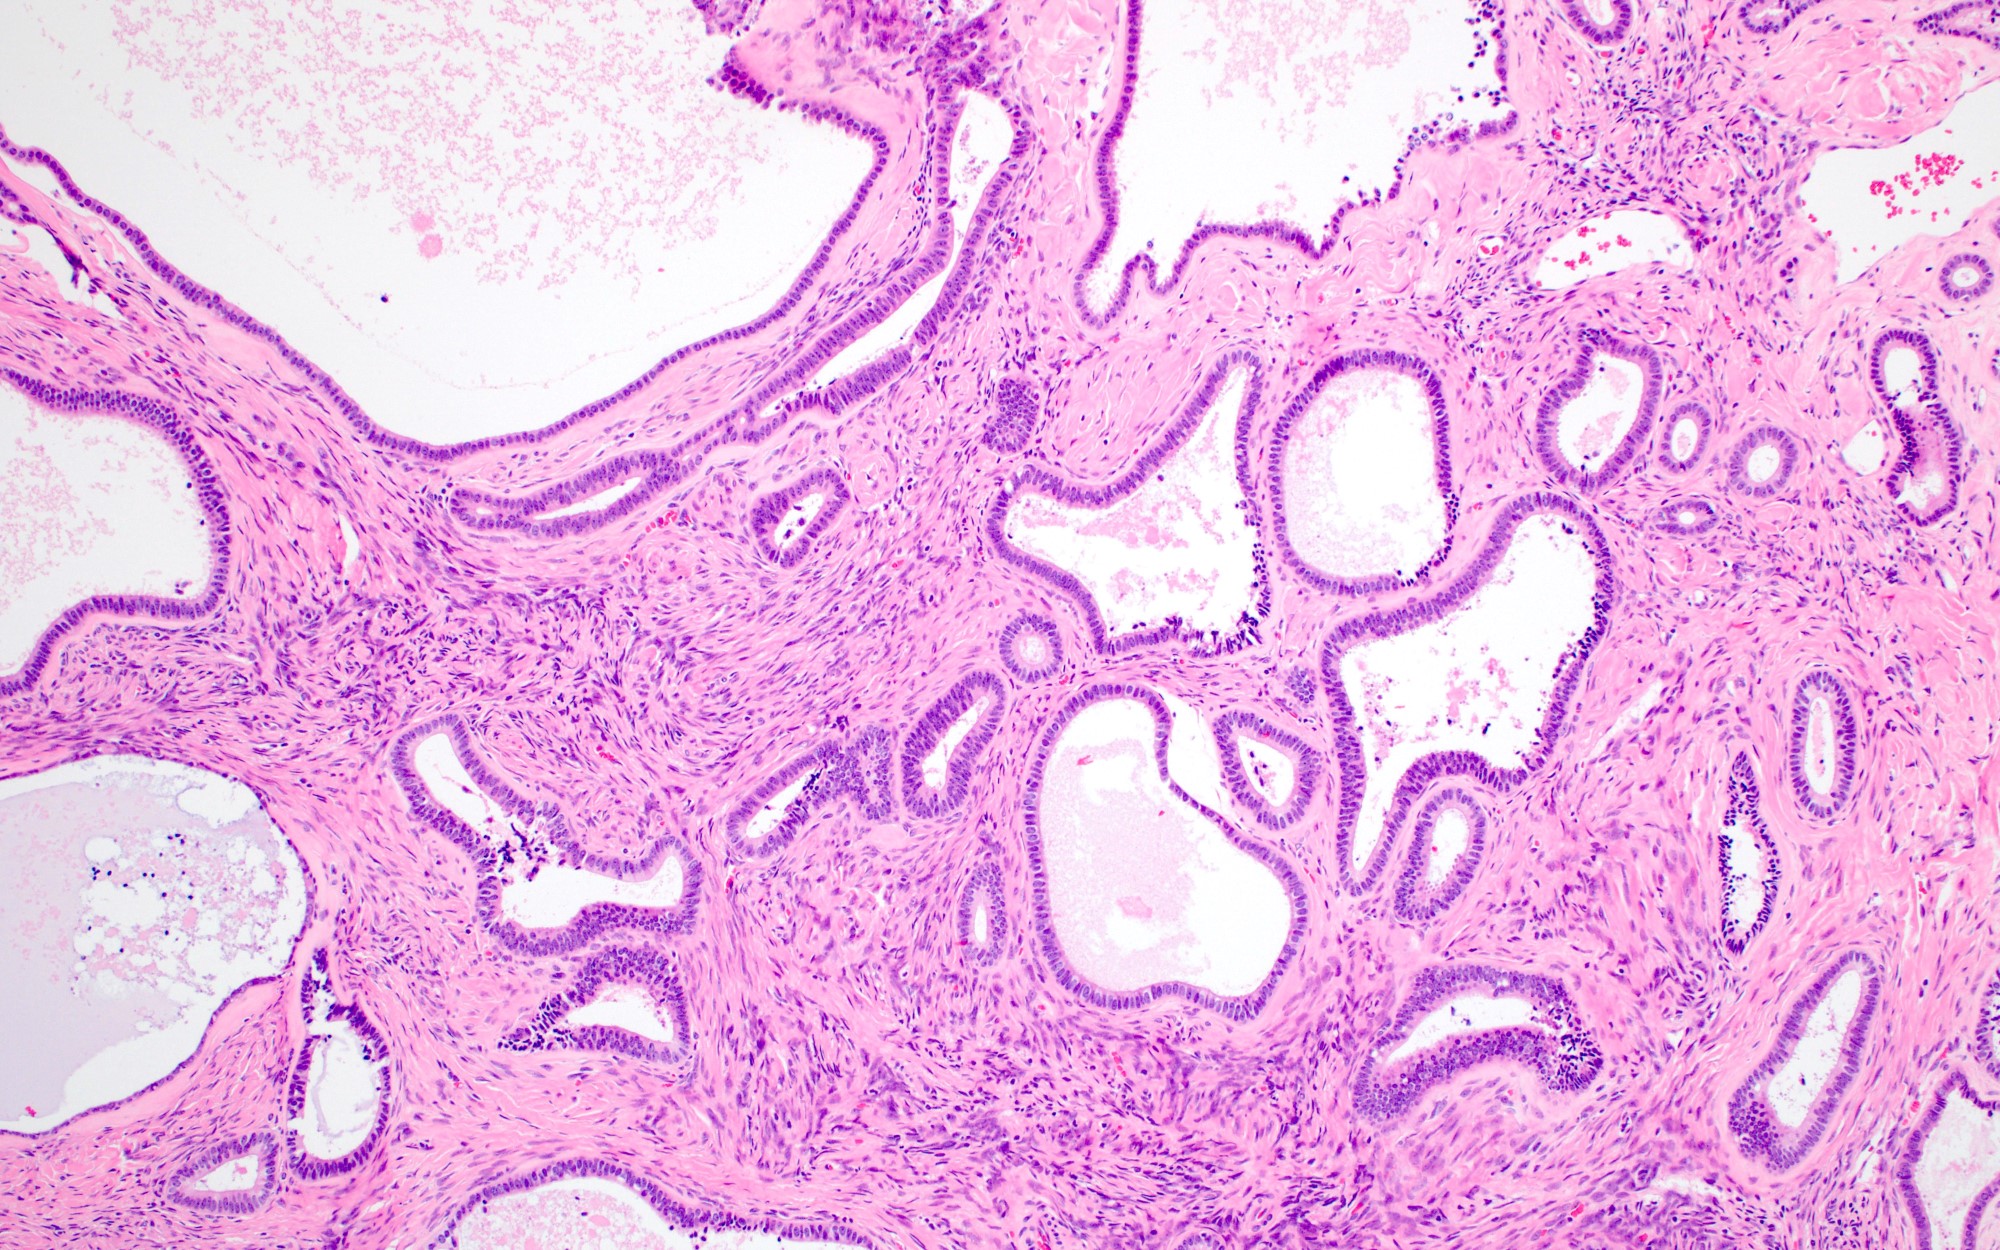

Microscopic (histologic) description

- Cystadenoma:

- Cyst lined by benign endometrioid epithelium without endometrial stroma

- Endometriosis may be present

- Adenofibroma:

- Widely spaced benign endometrioid glands associated with fibromatous stroma

- Endometriosis may be present

- Areas of mucinous or serous differentiation can be seen (Histopathology 2021;78:445)

Microscopic (histologic) images